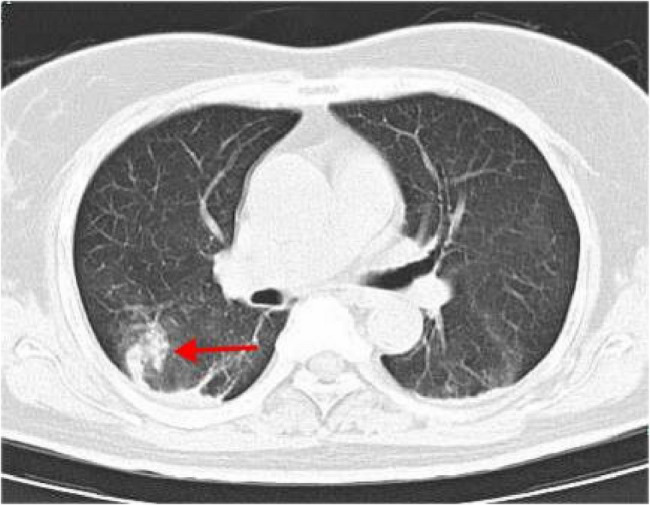

Ischemic bowel disease is a common disease of bleeding in the lower digestive tract. There are many risk factors for ischemic bowel disease. Abdominal pain, bloody stool and diarrhea were often the triad of clinical manifestations. The endoscopic appearance included colonic mucosal edema and erosion; submucosal hemorrhage, mucosal necrosis, mucosal shedding, ulcer formation et al. But in rare cases its manifestations are highly variable, which makes clinical diagnosis challenging. Colonoscopy and pathology are the keys to diagnosis. We present a case of "mass-forming" variant of ischemic colitis following COVID infection.